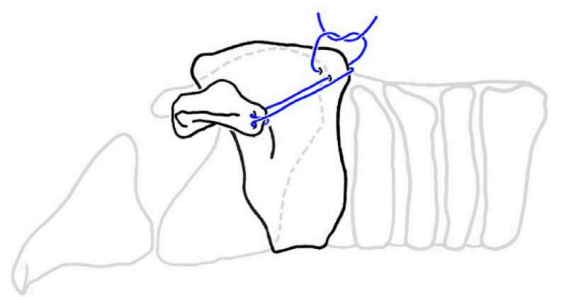

- 수술 (계속 반복될 시 고려) → unilateral arytenoid lateralization 추천

- 목 옆면에서 후두의 특정 연골을 잡아당겨 비대칭적으로 열어줌.

- 공기는 통과하지만 음식물은 통과하지 못하는 적절한 정도로 열어줌.